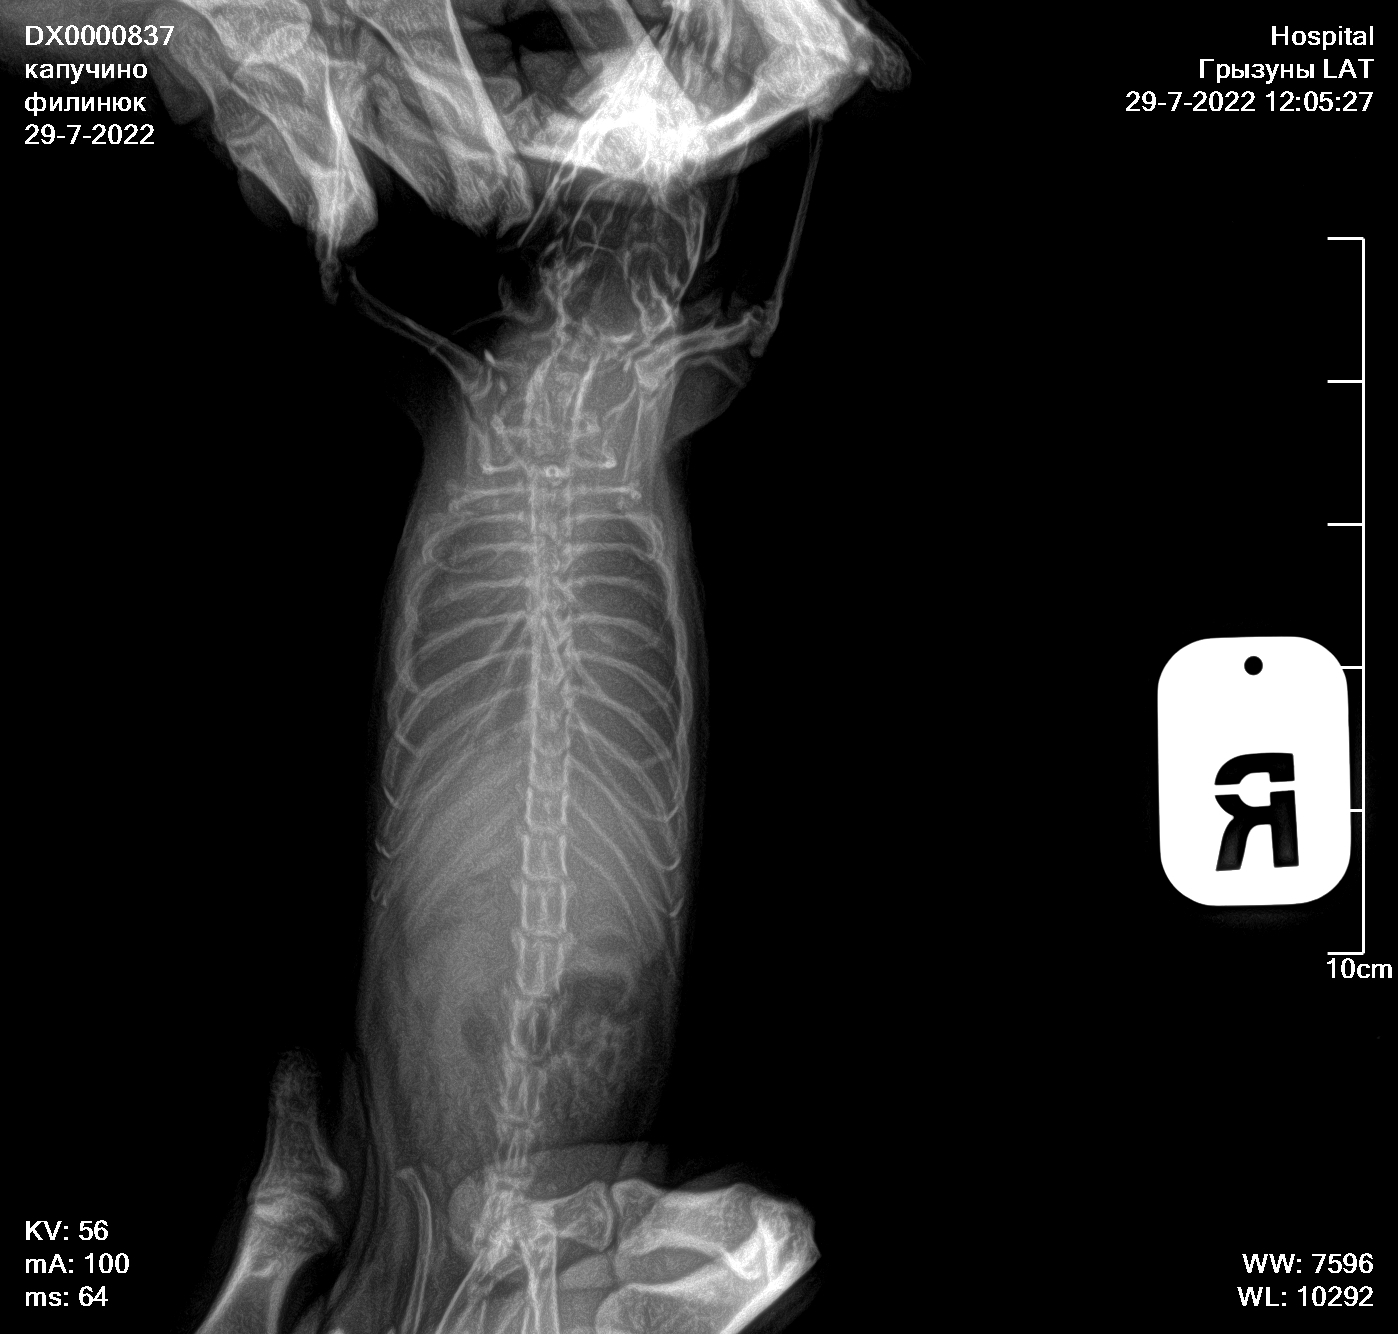

Сделали сегодня рентген новый, посоветовали попробовать продавать 5/5 асд-2 в течении 1-2 месяцев, посмотреть результат

Вложения

3feac979bae970f.jpg

4739d2500821714.jpg

АСД можете подавать, хуже не будет, но и эффекта вероятно не будет. Я когда-то его пробовала давать крысам, никаких результатов небыло, так что в эти сказки больше не верю. Антибиотик обязательно давать, преднизолон и фуросемид тоже.

По рентгену надо консультироваться на других форумах или вконтакте, где раньше консультировались, тут я никак не помогу, увы.